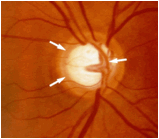

El glaucoma es una de las enfermedades oculares en la cual hay una lesión progresiva del nervio óptico, es decir el nervio que une el cerebro con el ojo, principalmente asociada al aumento de la presión intraocular, la cual va lesionando lenta y silenciosamente el nervio produciendo un daño progresivo del campo visual. Cuanto mayor sea la presión ocular el daño es mayor llevando a una ceguera irreversible, entre más temprano el glaucoma sea detectado y tratado por un oftalmólogo, mejor el pronóstico visual.

Dentro del ojo existe un líquido transparente llamado humor acuoso el cual se produce dentro del ojo y se evacua del ojo por un sistema de drenaje, el cual comienza a obstruirse y el liquido no encuentra una vía de salida, produciendo el aumento de la presión intraocular.

Existen varios tipos de glaucoma, los principales factores de riesgo son la edad avanzada, el aumento de la presión intraocular, la diabetes, la historia familiar de glaucoma, la miopía y la raza negra.

El glaucoma es una enfermedad incurable pero es controlable, los daños causados por glaucoma son irreversibles. La mayoría de glaucomas se controlan con gotas tópicas pero a veces se requiere de cirugía para el control de la presión intraocular.

La revisión periódica con un oftalmólogo puede prevenir la ceguera causada por esta enfermedad.